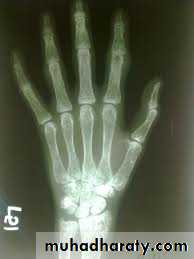

In rickets the changes are maximal where bone growth is occurring , so they are best seen at the knee, wrist and ankle .seen as

. Deficient the zone of provisional calcification .

.widening with irregularly mineralized metaphyses with cupping

.increase distance between the visible epiphysis & the calcified portion of the metaphysis .

.generalized decrease in bone density .

. Deformities of the bones occur because the under mineralized bone is soft , green stick fractures are common .